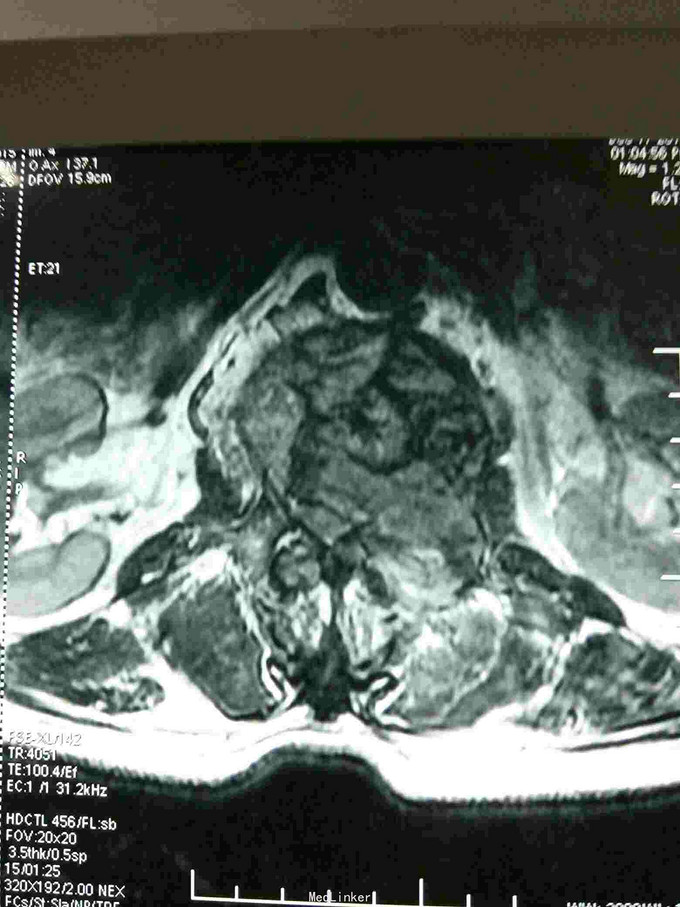

根据病史查体诊断:腰间盘突出症待确诊。应用消肿营养神经镇痛治疗。一天。查核磁共振示:腰椎多节段间盘突出伴椎管狭窄。第二腰椎骨破坏侵及椎板。部分突入椎管,脊髓受压。诊断:腰间盘突出伴椎管狭窄。第二腰椎转移癌,脊髓受压。经与家属沟通,查双肺CT:双肺下叶炎症。肺部纤维化。可见肿瘤阴影。肋骨及胸膜受累。胸椎部分骨破坏。最终诊断:双肺癌,胸椎,腰椎骨转移,脊髓受压。多节段腰椎间盘突出。病人至肿瘤科治疗。